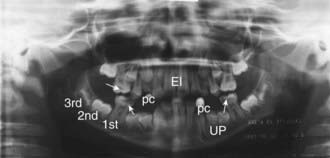

The panoramic radiograph provides a single tomographic image of the upper and lower jaw, including all the teeth and supporting structures. The x-ray tube rotates about the patient’s head with reciprocal movement of the film or image receptor during the exposure. The panoramic image shows the mandibular bodies, rami, and condyles; maxillary sinuses; and a majority of the facial buttresses. Such images are used to show abnormalities of tooth number, development and eruption pattern, cystic and neoplastic lesions, bone infections, and fracture, as well as dental caries and periodontal disease (see imageFig. 309-1 on the Nelson Textbook of Pediatrics website at www.expertconsult.com).

Figure 309-1 A panoramic radiograph of a 10 yr old child showing extensive dental caries of the 1st permanent molars (arrows), as well as normal structures: erupted 1st permanent molar, unerupted 2nd molar, and unerupted 3rd molar; erupted incisors (EI), unerupted permolars (UP), and erupted primary canines (pc).